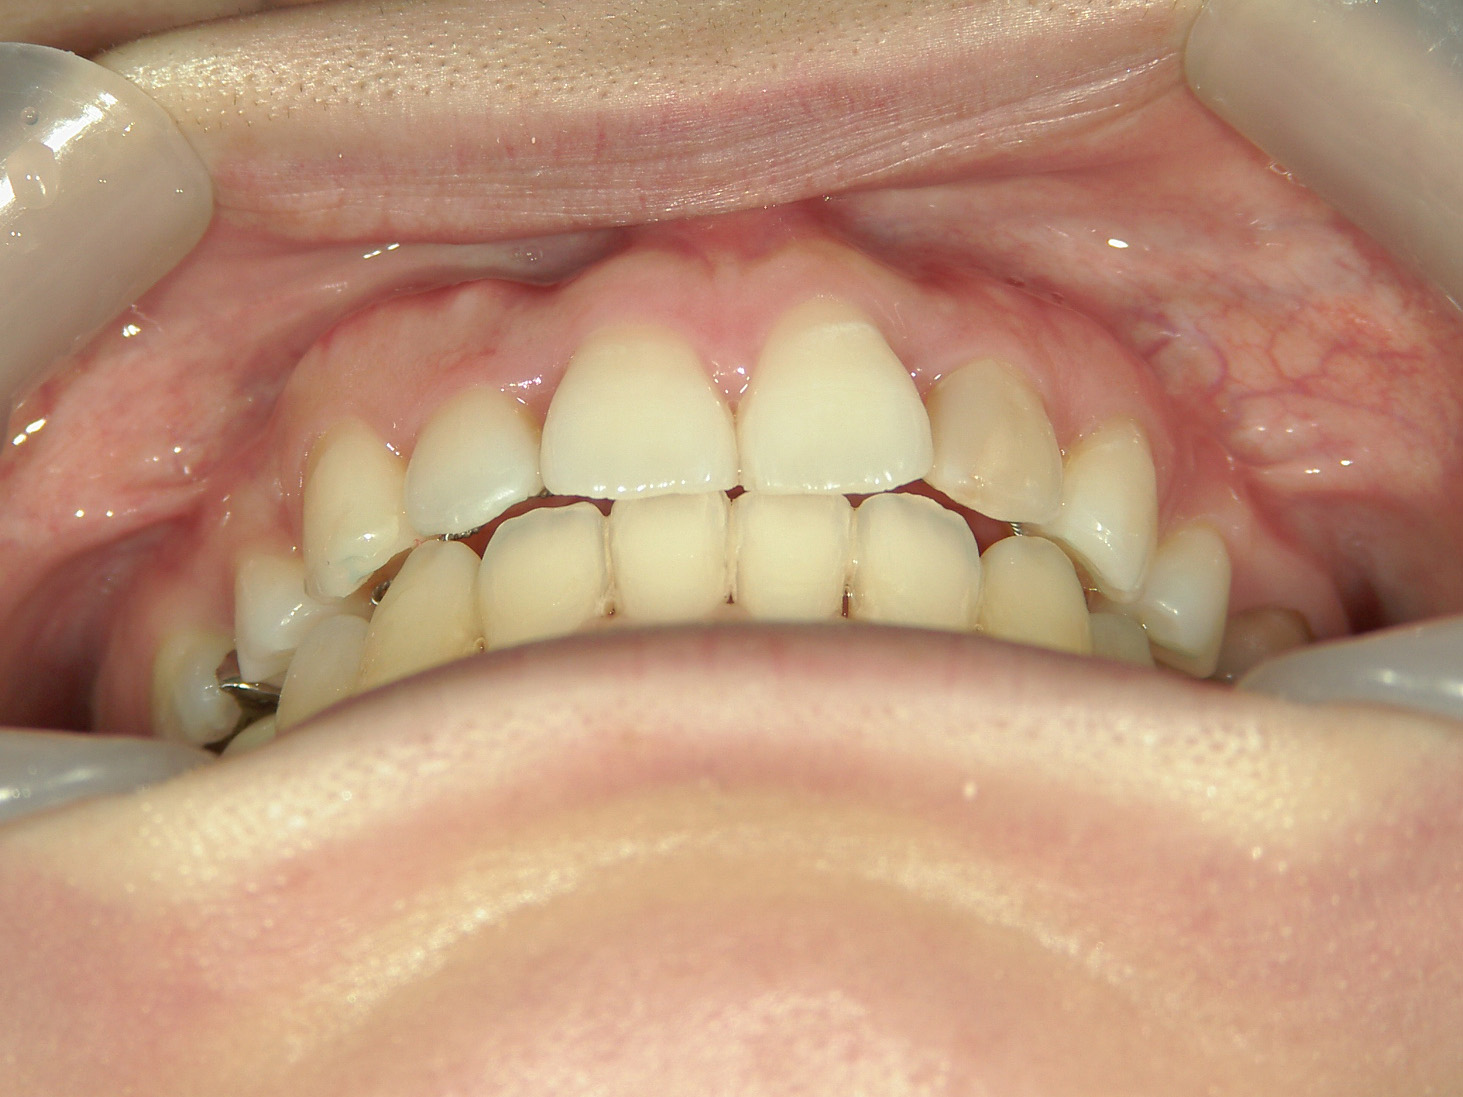

舌側ワイヤー矯正 症例(25)

主訴: 歯並びが気になる

| 治療期間 | 3年(矯正装置(BH・QH)併用期間も含む) |

| 費用 | 「診断料 27,500円」 「矯正装置代(BH・QH) 132,000円」 「治療代 1,100,000円」 「抜歯代(4本) 22,000円」 「ミニインプラント代(2本) 66,000円」 「月々の調整費 5,500円」 |

カテゴリー : ガタガタ(叢生)